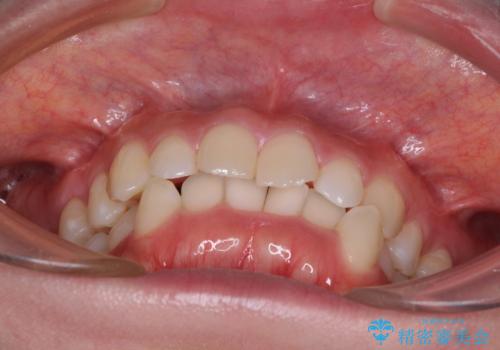

- 前歯のデコボコやクロスバイト、口元の突出感を気にして来院された患者様です。

上下左右の第一小臼歯4本を抜歯して、ワイヤー装置にて矯正治療を行うこととしました。